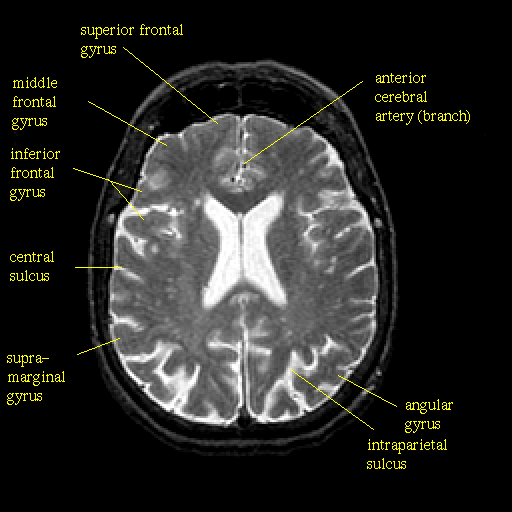

T2-weighted structural MR: Slice 33

Slice 33